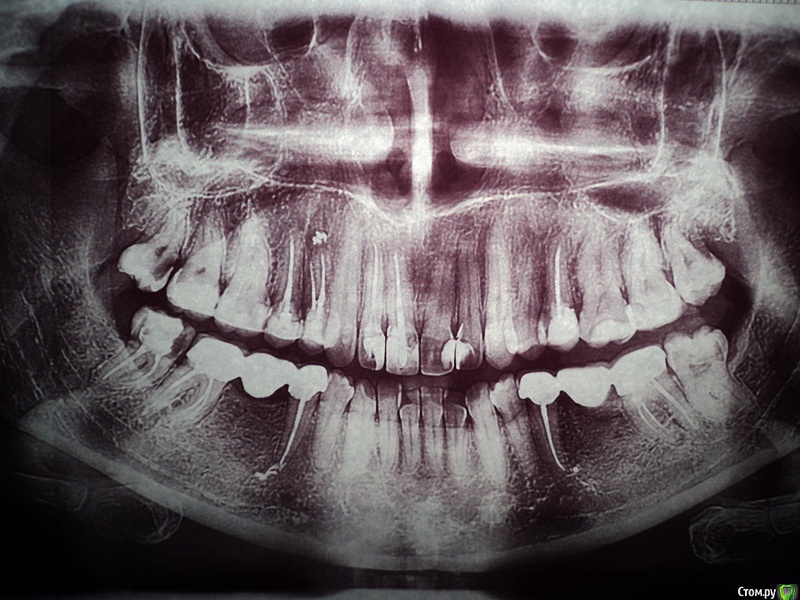

Анэйтис Опубликовано 5 февраля, 2015 Поделиться Опубликовано 5 февраля, 2015 (изменено) Добрый день!Четыре года назад мне были удалены 36 и 46 зубы (шестые нижние). Поставили мосты. Недавно начал ныть 37 зуб (нижний левый).Мост слетел. В 37 зубе - вторичный кариес. К тому же этот зуб, как выяснилось - наполовину пломба, наполовину сам дентин. Я опасаюсь, что если начать его лечение, остатки дентина могут отколоться до десны. И мост поставить будет, грубо говоря, не на что. Какие варианты лечения есть в таком случае? Можно ли сделать вкладку и на нее установить мост снова? Будет ли надежной такая конструкция, учитывая то, что зуб - жевательный. Очень хотелось бы услышать ваше мнение по поводу ситуации с 35, 37 и 45, 47 зубами.И еще очень интересуют 18, 28, 38, 48 зубы - удалять или еще что-то можно спасти? Изменено 5 февраля, 2015 пользователем Анэйтис Ссылка на комментарий

SDC Опубликовано 5 февраля, 2015 Поделиться Опубликовано 5 февраля, 2015 Добрый день!Четыре года назад мне были удалены 36 и 46 зубы (шестые нижние). Поставили мосты. Недавно начал ныть 37 зуб (нижний левый).Мост слетел. В 37 зубе - вторичный кариес. К тому же этот зуб, как выяснилось - наполовину пломба, наполовину сам дентин. Я опасаюсь, что если начать его лечение, остатки дентина могут отколоться до десны. И мост поставить будет, грубо говоря, не на что. Какие варианты лечения есть в таком случае? Можно ли сделать вкладку и на нее установить мост снова? Будет ли надежной такая конструкция, учитывая то, что зуб - жевательный. Очень хотелось бы услышать ваше мнение по поводу ситуации с 35, 37 и 45, 47 зубами.И еще очень интересуют 18, 28, 38, 48 зубы - удалять или еще что-то можно спасти? Здравствуйте.Снимок, который Вы предоставили слишком контрастный, по этому снимку можно запросто ошибиться с первичной диагностикой кариеса зубов, но похоже, что 8-е зубы сохранять просто незачем.Тем не менее, правильным вариантом будет:имплантация в области отсутствующих нижних 6-х зубов и одиночные коронки на 5-е и 7-е зубы.Стоит подумать о протезировании коронками 15, 14, 25 зубов. Ссылка на комментарий

Гарриевич Опубликовано 14 февраля, 2015 Поделиться Опубликовано 14 февраля, 2015 Сделайте прицельные снимки интересующих зубовПо этому снимку кажется, что нужно перелечивать 37 Ссылка на комментарий